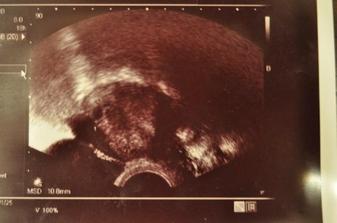

Skusali sme od Juna 2009, a na konci roka v decembri sa predsa len stastie usmialo aj na nas :D

Uz od 11tt vdaka genetonu vieme, ze cakame chlapca 🙂